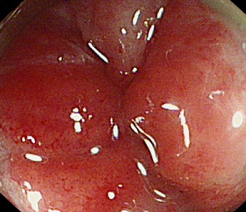

术前

术中